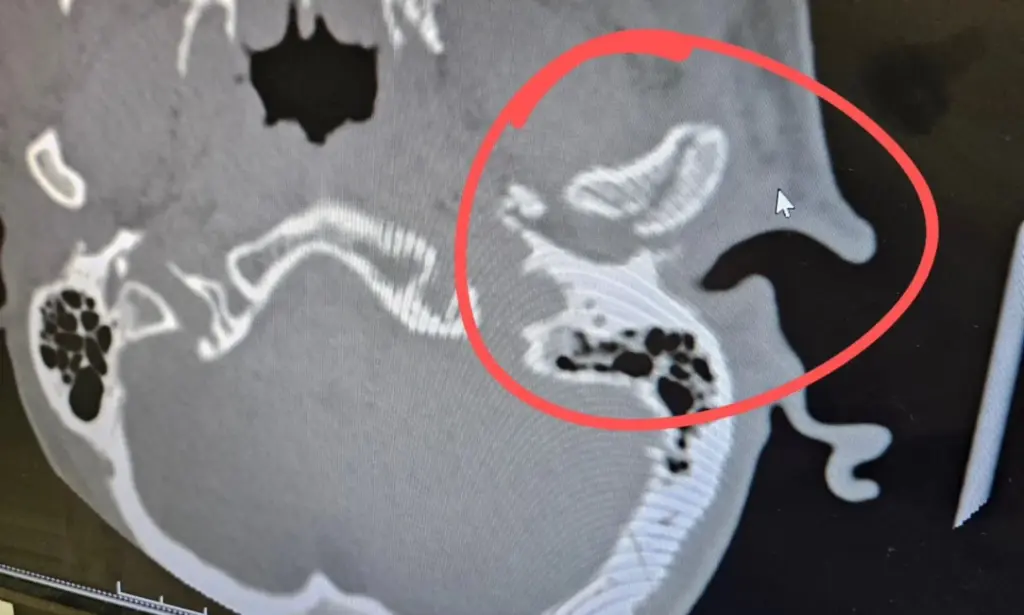

Ο εργάτης οικοδομών μεταφέρθηκε στο Dell Seton Medical Center, όπου οι αξονικές τομογραφίες αποκάλυψαν ότι είχε υποστεί κάταγμα στο σαγόνι και διάσειση. Οι ιατροδικαστές βρήκαν ένα θραύσμα από το σαγόνι του στο αυτί του, το οποίο ήταν γεμάτο αίμα.